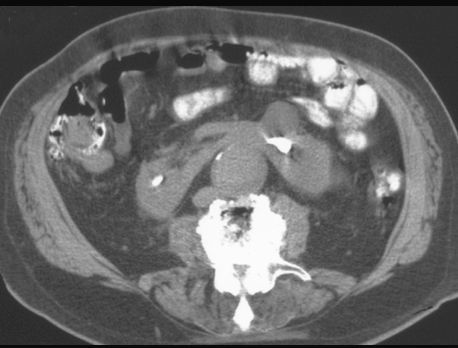

NERKA PODKOWIASTA

TK